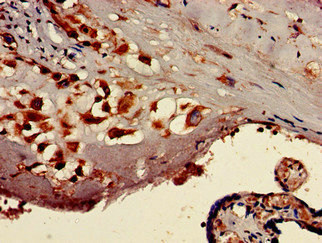

Immunohistochemistry of paraffin-embedded human glioma using CSB-PA757569LA01HU at dilution of 1:100

Immunohistochemistry of paraffin-embedded human placenta tissue using CSB-PA757569LA01HU at dilution of 1:100